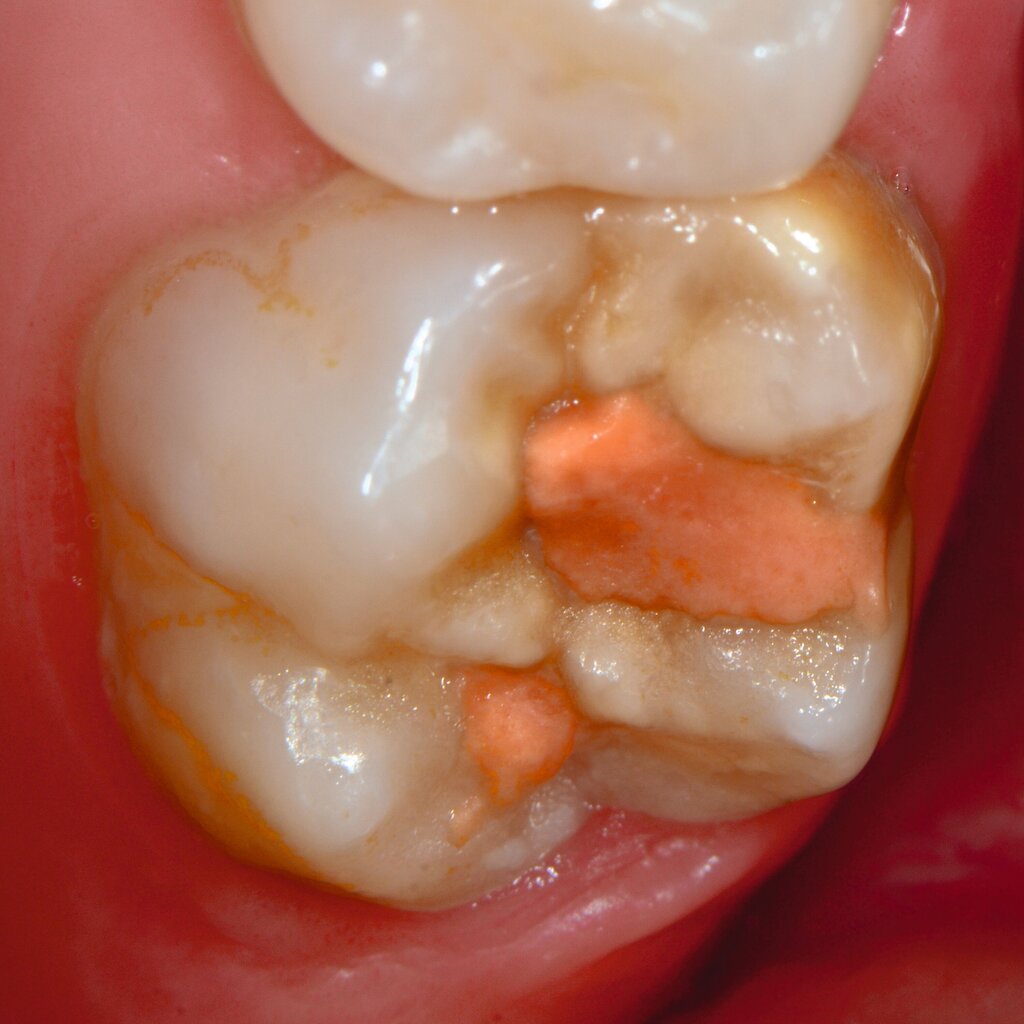

An umfangreich hypomineralisierten Zähnen können Schmelzeinbrüche (engl.: „enamel breakdown“ oder „enamel desintegration“, Abbildung 5) auftreten [Lygidakis et al., 2010; 2022]. Da diese oftmals die Folge einer fehlenden Belastungsfähigkeit des Zahnschmelzes sind und erst nach der Einstellung der Zähne in die Okklusion auftreten, werden sie auch als posteruptive Schmelzeinbrüche bezeichnet. Sie sind häufig im Bereich der Kauflächen beziehungsweise Höcker der Molaren zu finden, führen zur Dentinexposition und damit einhergehend zu ausgeprägten Hypersensitiven insbesondere bei Kindern, deren Zähne gerade erst durchgebrochen sind [Linner et al., 2021].

Bei post- beziehungsweise präeruptiven Oberflächendefekten ergibt sich in einigen Fällen die Indikation zur Restauration dieser MIH-Zähne. Unter Verweis auf die Lokalisation von MIH-bedingten Hypomineralisationen außerhalb der typischen Kariesprädilektionsstellen – zum Beispiel okklusale Fissuren und Grübchen oder Approximalflächen – werden diese als „atypische Restaurationen“ (engl.: „atypical restoration“, Abbildung 6) klassifiziert. Als ein weiteres Erkennungsmerkmal gilt die Präsenz von Hypomineralisationen im Bereich der Restaurationsränder. MIH- und kariesbedingte Restaurationen können und sollten sicher voneinander abgegrenzt werden.